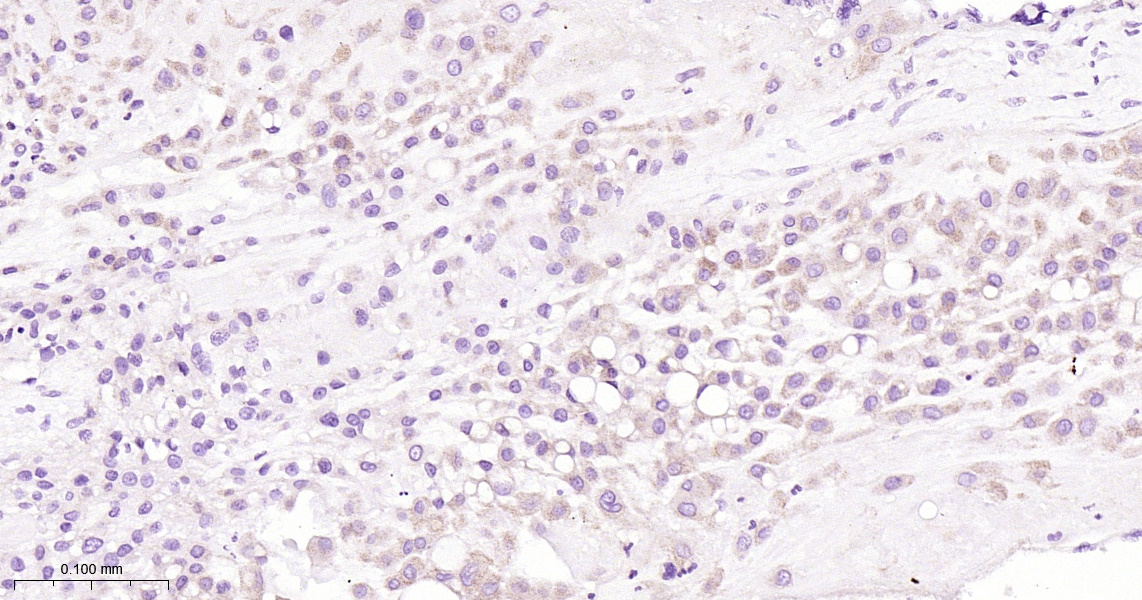

• IHC-P

IHC-P IHC-P1:50-200